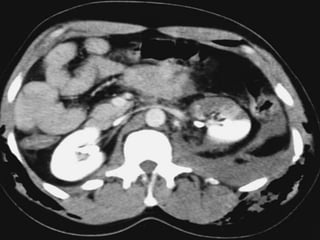

Computed tomography

Imaging study of choice for hemodynamically stable

patient

Sensitive and specific

Advantages

(1) Functional and anatomic assessment of the kidneys

and urinary tract

(2) Establish the presence or absence of 2 functional

kidneys

(3) Diagnosis of concurrent injuries

(4) Delineates extravasations, segmental infarcts, and

hematoma

Disadvantages

(1) Requires intravenous contrast

(2) Patient must be stable enough

(3) Full urinary assessment is dependent on the timing

of contrast and scanning in order to view the bladder

and ureters.